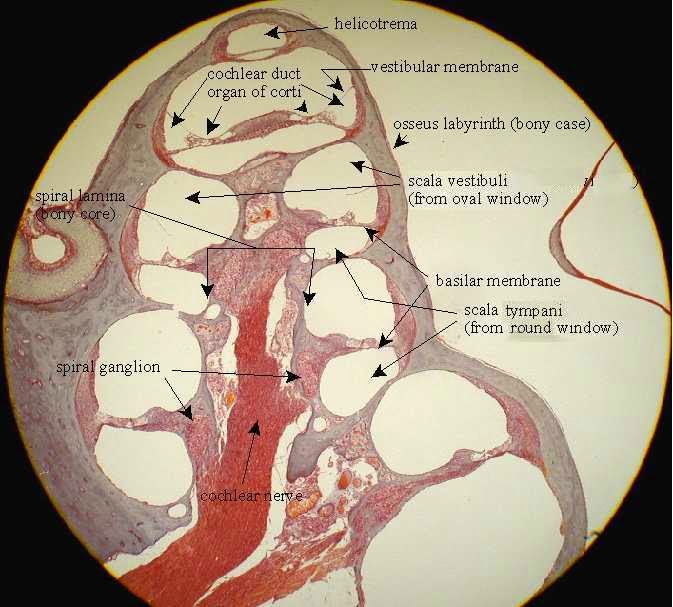

Ducts Cochlea Diagram